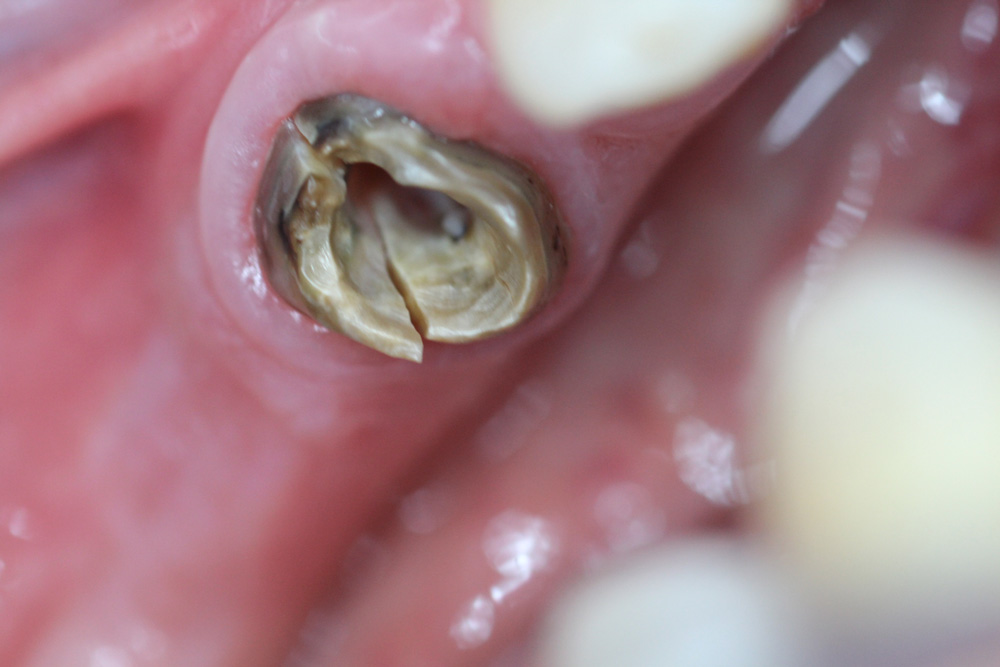

C’est initialement en endodontie (soins des racines dentaires, lorsque la dent ne peut plus être conservée vivante) que le microscope a trouvé son argument majeur. Les soins endodontiques sont spécifiques dans la mesure où ils sont effectués à l’intérieur de la cavité pulpaire de la dent : le praticien travaille en aveugle, en se basant uniquement sur sa perception tactile. Grâce au microscope «l’oeil est transporté au bout du doigt» permettant à l’opérateur d’observer et de diriger finement le travail de ses instruments à l’intérieur des racines. Les séances de traitements de racines, réputées longues, difficiles, éprouvantes pour le dentiste et le patient et caractérisés par des résultats aléatoires, deviennent ainsi beaucoup plus fiables. Le microscope trouve ici un domaine d’intervention majeur en apportant confort de travail pour le praticien et bénéfice pour le patient, grâce à un réel gain en terme de fiabilité et de prédictibilité du résultat endodontique. De surcroît, le microscope permet des prouesses techniques telles que l’élimination d’instruments cassés à l’intérieur des racines, le comblement de perforations dentaires, l’obturation canalaire des racines immatures et résorbées....

En odontologie conservatrice, la pratique des soins restaurateurs s’en trouve significativement bouleversée. Les cavités de caries peuvent être traitées par de nouvelles méthodes moins mutilantes. Grâce au contrôle visuel permanent, le chirurgien dentiste bénéficie d’une action très sélective : il parvient à n’éliminer que les seuls tissus dentaires cariés, en réalisant des minicavités et des miniobturations dentaires préservant ainsi la résistance mécanique des dents, moins susceptibles de se fracturer ultérieurement. La mise en place des matériaux de restauration dentaire, en particulier des matériaux adhésifs, est également facilitée : la qualité des joints augmente, permettant des obturations plus étanches moins sujettes aux sensibilités post-opératoires et aux récidives de caries. La finition et le polissage des résines composites sous microscope permettent de rendre les obturations quasiment invisibles. Ainsi, microdentisterie est aussi synonyme d’esthétique.